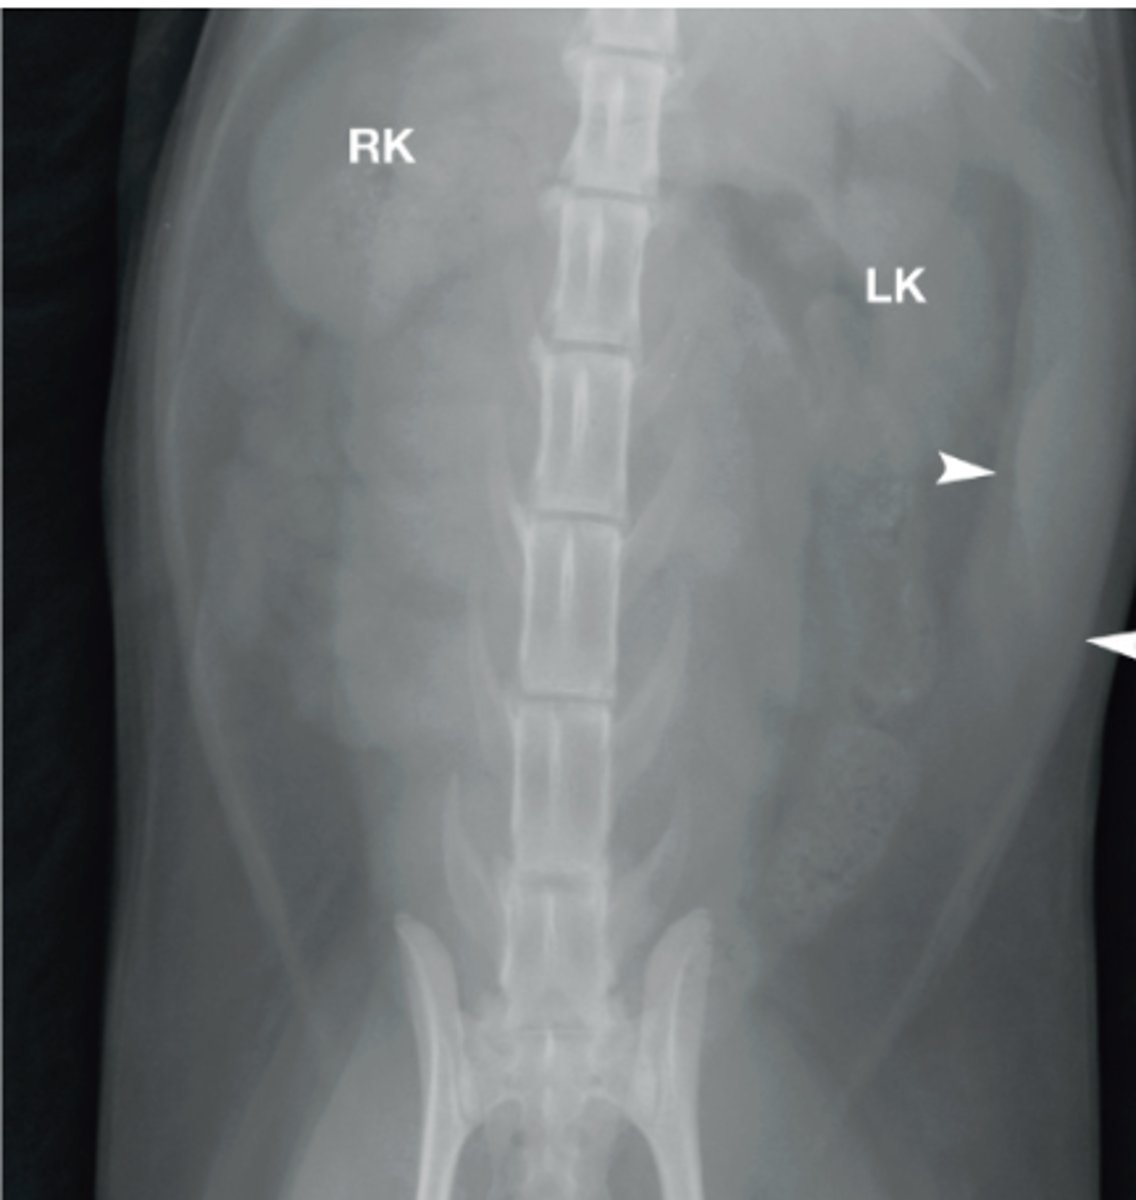

Renomegaly

Cat image with large kidneys and ureters- what is this called?

left kidney

What structure is this?